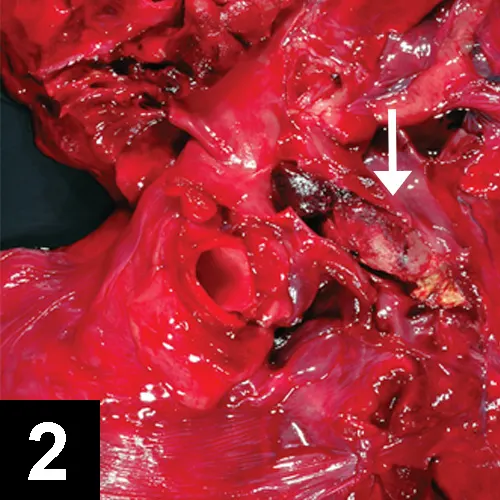

A close-up view of a dissected canine thoracic cavity, showcasing the heart and surrounding tissues in vivid red coloration. An arrow points to a specific area of interest, highlighting a potential pathological finding within the anatomical structures.

FIGURE 2

Thrombus (arrow) in pulmonary artery

• Postmortem findings may show in situ thrombus (Figure 2).